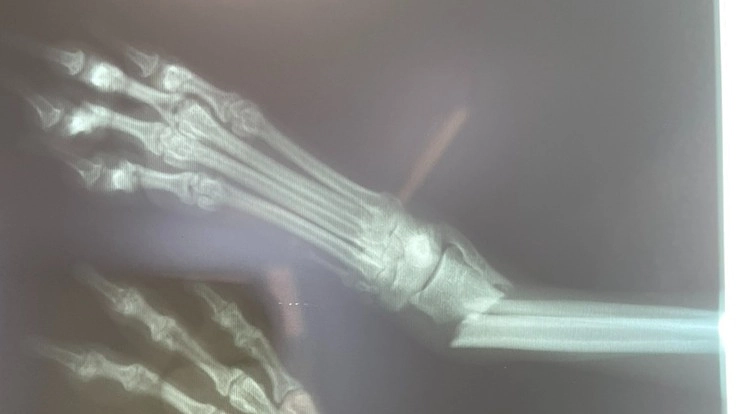

連れて来た時には右脚プラプラ。 あれ? これはもしかして…と思い、

すぐ病院へ。

案の定「骨折しています」と…。

治療・手術内容 右前足の骨折。切開をして鉄板を入れボルトで止める手術。